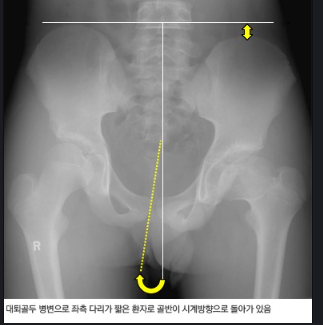

ㅁㅁ무릎의 높낮이가 차이가남.......

장단족을 검사 했는데 길이가 5센티 이상 차이가 나는 것같아 근육풀고 교정하고 운동요법 정골 요법 등을 교정했더니 3주만에 극심한

장요근 검사도 하고 서비스 받고 나서 장단족 길이가 많이 좁아진 상태 에있고